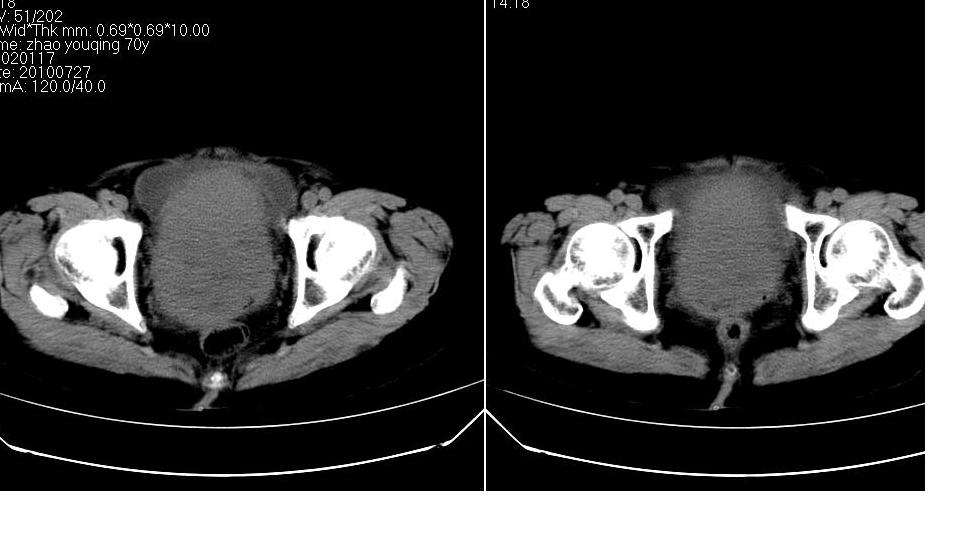

女,70岁,十天前在上级医院确诊宫颈癌,具体病史不详。

子宫形态增大,其内密度不均匀,宫颈部未见异常

子宫形态增大,其内密度不均匀,宫颈部未见异常,建议增强。

子宫体积增大,其内密度不均,考虑子宫内膜癌侵犯宫颈

宫颈癌阻塞性宫腔积液?累及宫腔?